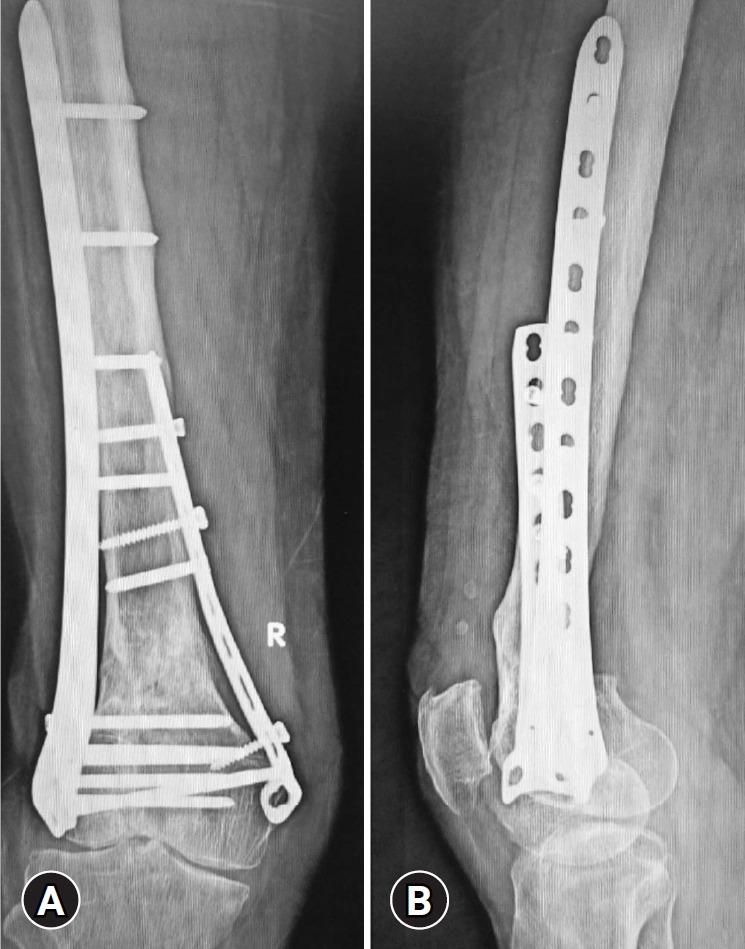

This study investigated 24 aseptic and 3 septic nonunions of distal femur fractures, classified as AO/OTA type C, that were previously managed with open reduction and internal fixation using only a lateral locked plate. Revision surgery involved replacing the broken 5.0-mm lateral locked plate, supplementing the medial side with a 4.5-mm T-plate, and applying bone grafting at the fracture site. Septic cases were managed using a staged approach with dual implant application.

Following revision surgery, bony union was achieved in 83.3% of aseptic nonunions, with a mean bone healing time of 22.5 weeks (range, 15-27 weeks). Additional surgery was required for the remaining 16.6%. Using staged management, the septic nonunions were united in a mean of 30.25 weeks (range, 27-32 weeks). Significant improvements were noted in the Tegner Lysholm Knee Scoring Scale, with median preoperative and postoperative scores of 30 (range, 12-67) and 80 (range, 66-90), respectively (P<0.001). Limb pain, as measured by the visual analog scale for knee pain, improved significantly from a preoperative median of 6 (range, 4-8) to 3 (range, 1-6) postoperatively (P<0.001). All patients were ambulatory without supportive devices. However, the mean knee range of motion was 80° (range, 40°-120°). Limb shortening was observed in six cases (22.2%; average shortening, 2.3±1.0 cm).

方法

本研究调查了24例无菌性和3例感染性股骨远端骨折不愈合病例,均为AO/OTA C型,此前仅使用外侧锁定钢板进行切开复位内固定治疗。翻修手术包括更换断裂的5.0毫米外侧锁定钢板,在内侧补充一块4.5毫米的T形钢板,并在骨折部位进行植骨。感染病例采用分期双钢板置入的方法处理。

翻修手术后,83.3%的无菌性不愈合实现了骨愈合,平均骨愈合时间为22.5周(范围15 - 27周)。其余16.6%的患者需要再次手术。采用分期处理,感染性不愈合平均在30.25周(范围27 - 32周)实现愈合。Tegner Lysholm膝关节评分量表有显著改善,术前和术后中位数评分分别为30(范围12 - 67)和80(范围66 - 90)(P<0.001)。通过膝关节疼痛视觉模拟量表测量的肢体疼痛,术前中位数为6(范围4 - 8),术后显著改善至3(范围1 - 6)(P<0.001)。所有患者无需辅助装置即可行走。然而,膝关节平均活动范围为80°(范围40° - 120°)。6例(22.2%)出现肢体短缩(平均短缩2.3±1.0厘米)。